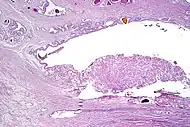

Intraductal adenocarcinoma 2.8%[10]

H&E and CK5/6

• Carcinoma cells spanning entire lumen of ducts and acini[11]

• At least focal preservation of the basal cell layer[11]